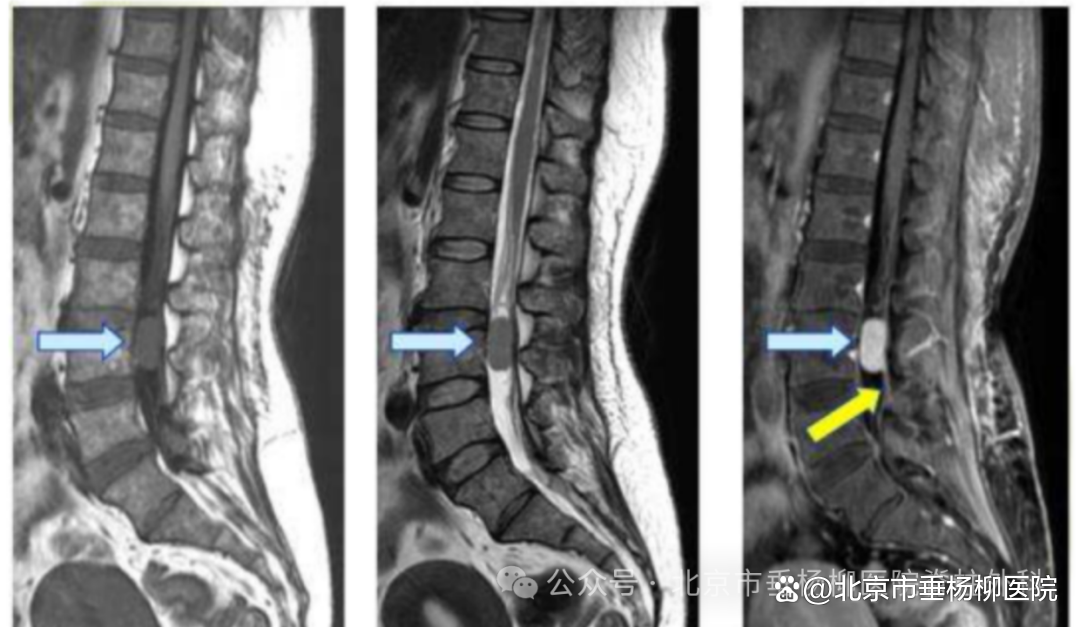

▲C3/4水平椎管内占位,考虑脊膜瘤可能

▲术后影像

脊膜瘤在MRI上特征性的图像为在增强MRI上出现的“硬膜尾征”,肿瘤局部的硬脊膜增厚,呈现线样强化并与肿瘤紧密相连。图中黄色箭头像尾巴一样的亮线条就是“硬膜尾征”。